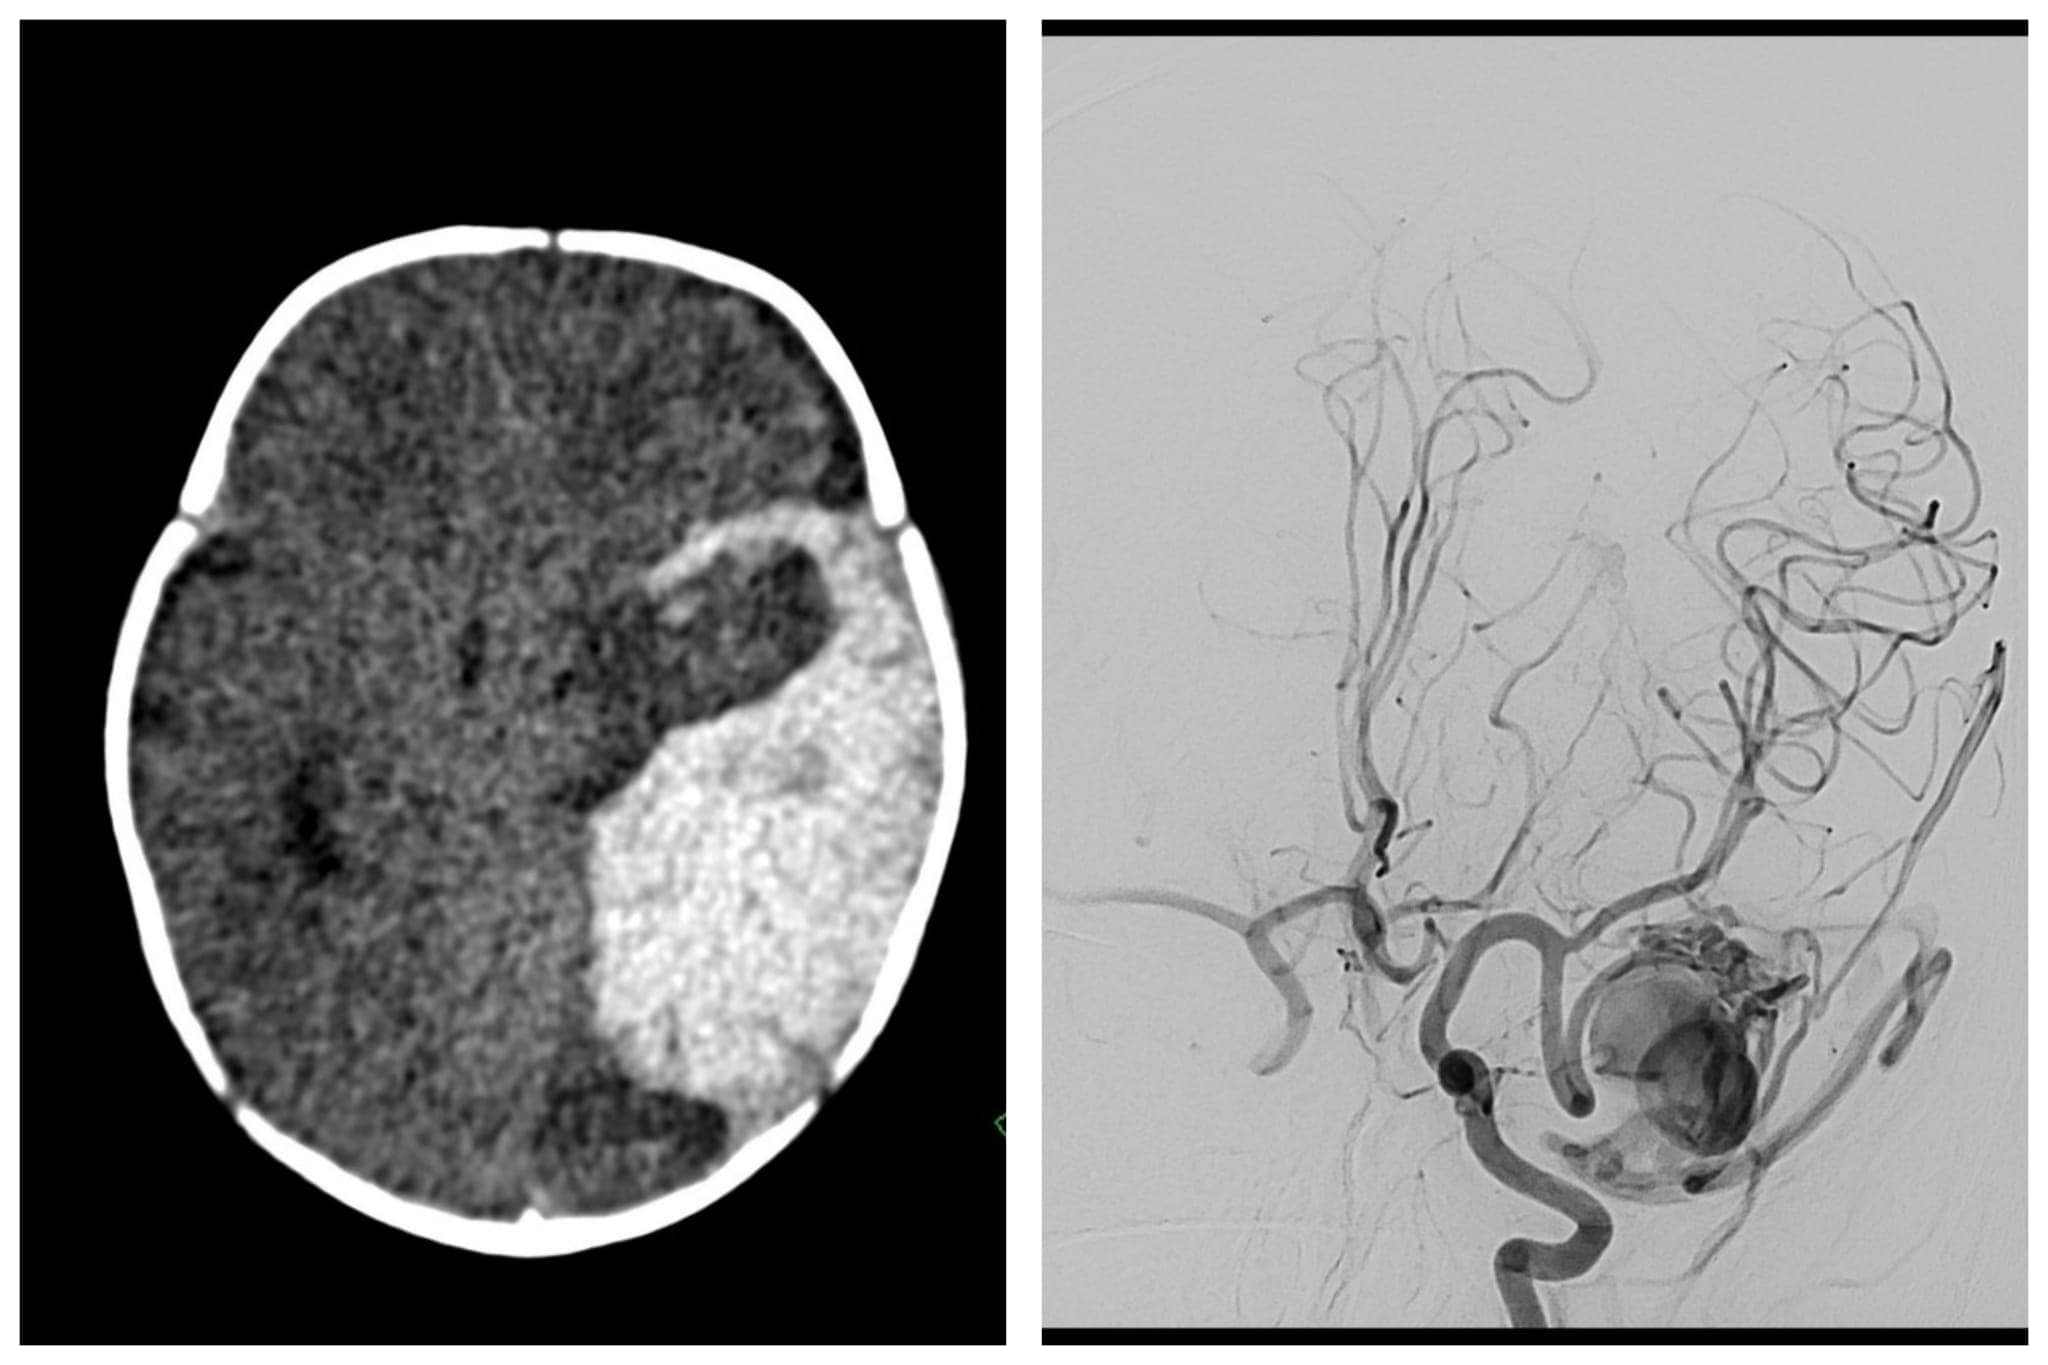

א', תינוק בן חודשיים, סבל מבכי שאינו פוסק ואי שקט מזה מספר ימים. לפני מספר שבועות, הוריו של התינוק הביאו אותו לבית החולים שערי צדק בשעות הערב, כאשר הוא סובל מחולשה קלה וירידה תפקודית. לאחר שא' עבר בדיקות וסריקת CT ראש, התגלה שהוא סובל מדימום משמעותי בצד שמאל של המוח. בסריקת CT Angio (סריקה המכוונת לכלי הדם במוח), הועלה החשד להתפתחות לא תקינה בקשר בין העורקים והוורידים במוח.

בבוקר למחרת התינוק עבר צנתור מוח דחוף בהרדמה מלאה והתגלה כי הוא סובל ממלפורמציה עורקית ורידית (AVM), חיבור מולד לא תקין בקשר בין העורקים לוורידים בצד שמאל של המוח, בניגוד למצב התקין של קשר בין העורקים הנימים הורידים. מחלה זו יכולה להוביל לדימום במוח ששכיחותו מוערכת בין 2%-6% בשנה.

לאחר שלושה שבועות התינוק עבר מספר הדמיות והוחלט שהוא מתאים לטיפול בצנתור לסגירת המלפורמציה. הצנתור התבצע על ידי ד"ר יעקב אמסלם, מנהל יחידת צנתורי מוח בבית החולים שערי צדק וצוותו. הטיפול התבצע בהרדמה מלאה וערך כארבע שעות. הצנתור עבר בהצלחה, המלפורמציה נסגרה על ידי דבק במלואה, התינוק הוער בחדר הצנתורים ונראה חיוני ויציב ללא חסר ניורולוגי חדש, לאחר אשפוז של יום בטיפול נמרץ ילדים ויום נוסף במחלקה כירורגית ילדים, התינוק השתחרר לביתו.